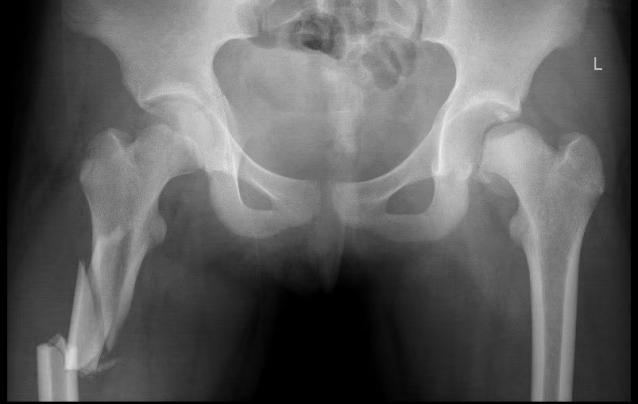

1个多月前,11岁的小张不慎从约20米高的楼上掉下,导致脑挫裂伤、胸部闭合性损伤、脾破裂、左侧髋臼骨折、左侧股骨颈骺分离、右侧股骨粉碎性骨折等多处骨折,情况危急,被紧急送入二一五医院进行救治。入院后,医务人员立即在介入下为其进行脾动脉栓塞,输血、补液等紧急对症治疗,并严密监护生命体征。

与此同时,小儿骨科·创伤骨科潘建宏主任第一时间带领团队对小张的病情进行了全面检查与评估,经诊断,明确了小张的骨折属于右侧股骨上段粉碎骨折,左侧股骨颈骺分离、Delbet分型Ⅰa型、Salter_ HarrisⅠ型骨骺损伤,骨折的股骨头骺端脱位于髋臼后侧。而这种骨折约占儿童所有骨折的万分之五,非常少见,并且手术难度大、风险大、预后差。